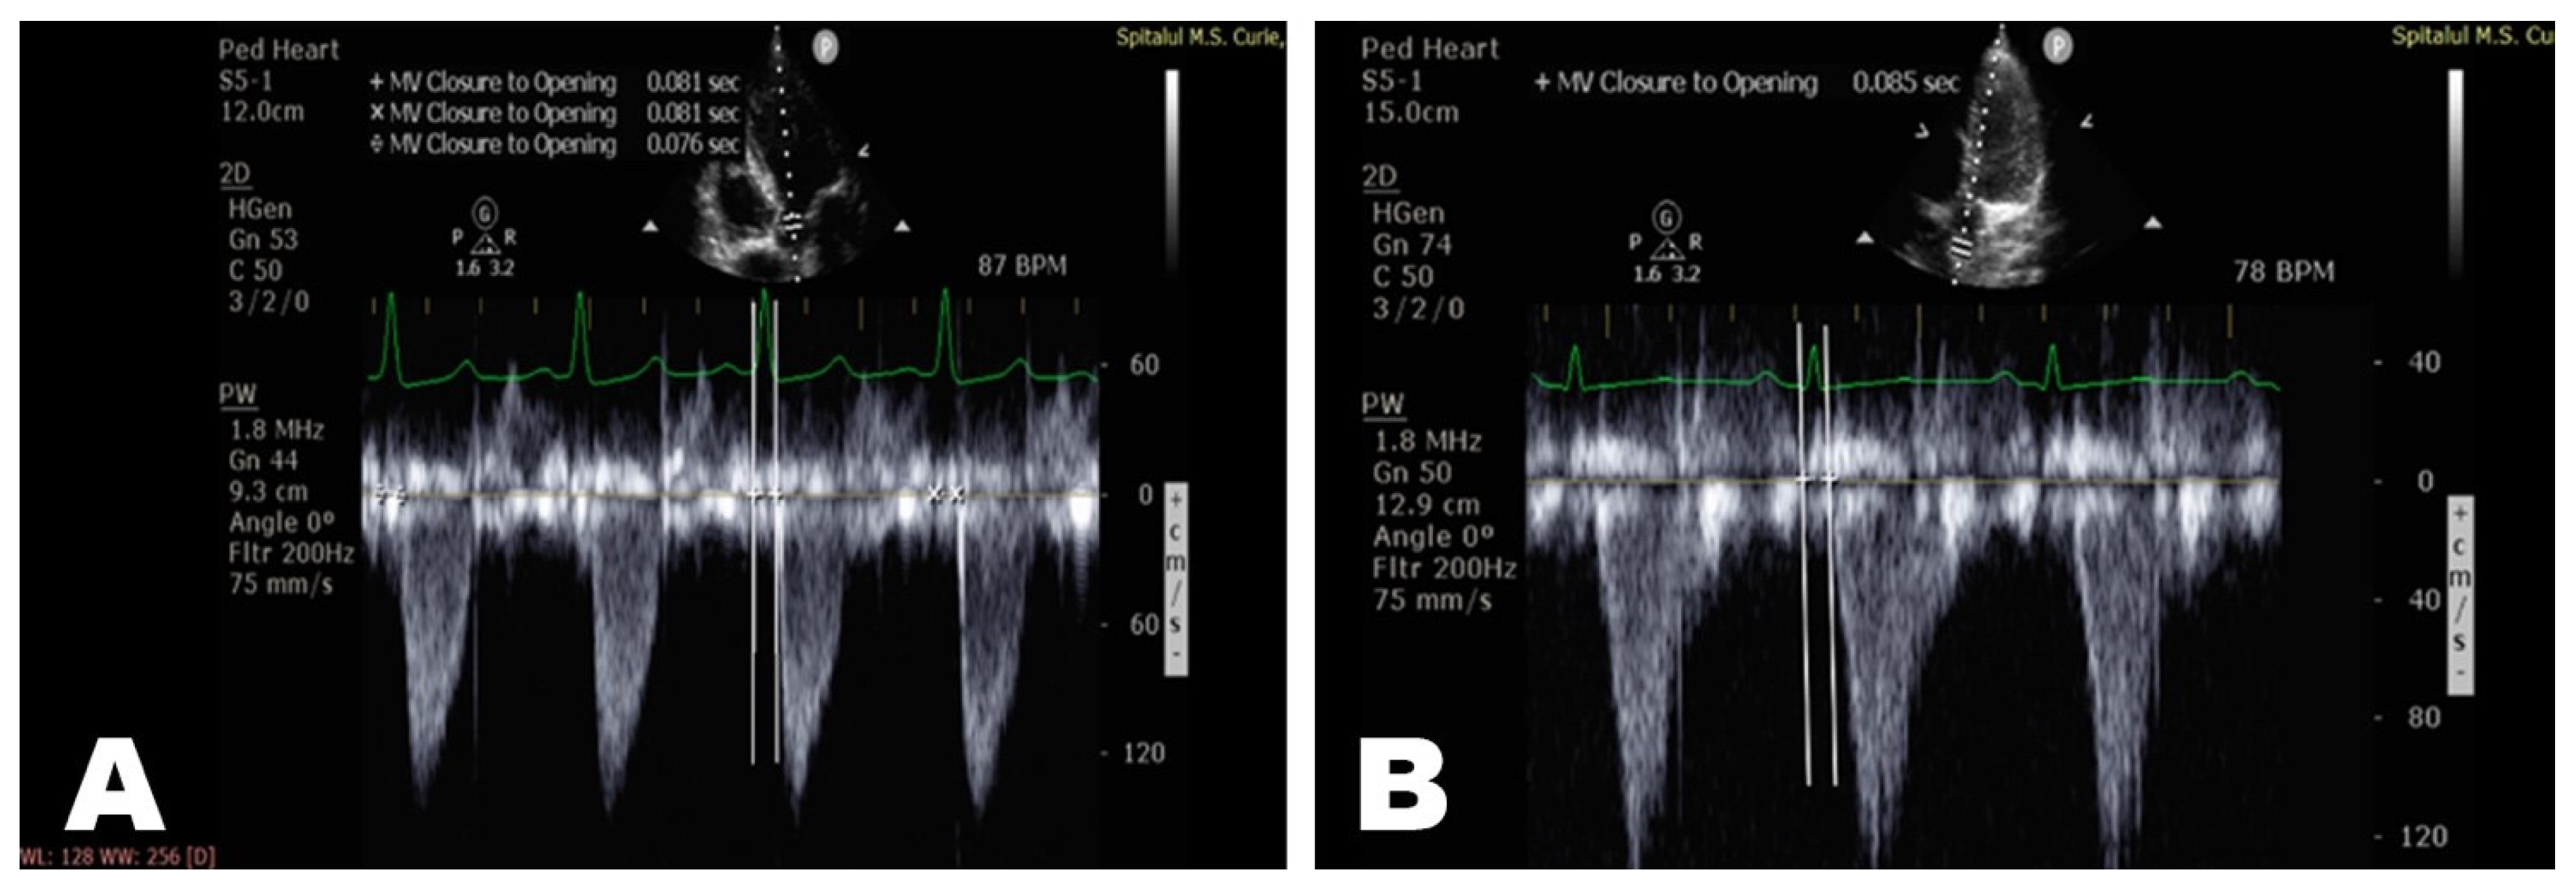

| T0(QRS—AoV) (msec) | 70 [63.9;80.1] | 65.7 [63.75;72] | 74.47 [60;92] | 72 [64;80] |

| T1(QRS—AscAo) (msec) | 75 [67;84] | 70.8 [69.75;75.25] | 80.18 [66;97.5] | 76.6 [67;84] |

| T2(QRS –DescAo) (msec) | 109 [98.9;117.1] | 107.3 [104.3;115] | 118.8 [101;136] | 104 [92;113] |